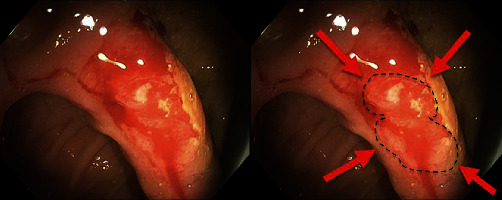

Nonsteroidal anti-inflammatory drugs (NSAIDs) are commonly used to reduce pain and inflammation in over 30 million individuals daily. Gastrointestinal bleeding (GIB) associated with NSAID consumption has been well documented in gastric and duodenal bleeding; however, NSAID-associated GIB distal to the duodenum lacks extensive documentation. This report highlights small bowel occult bleeding related to NSAID use in a patient with a surgical history of robotic total colectomy with ileorectal anastomosis completed 1 year prior. In the case of bright red blood per rectum with associated NSAID use, we recommend NSAID cessation followed by an individualized treatment plan, such as upper/lower endoscopy and/or angioembolization.